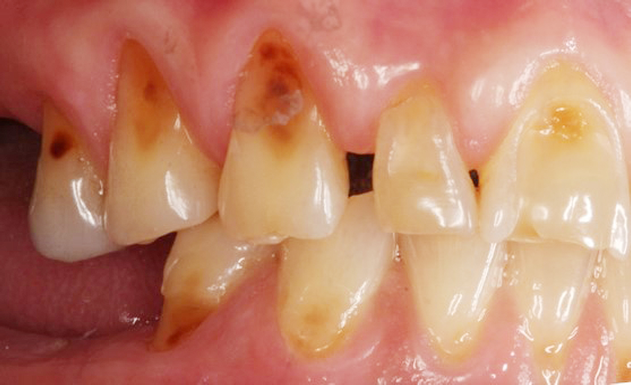

The BEWE is a scoring system that evaluates the most severely affected surface in each sextant, recording one of the four-level scores as follows30: 0 = no erosive tooth wear (Figure 8); 1 = initial loss of surface texture (Figure 9); 2 = distinct defect, hard-tissue loss <50% of surface area (Figure 10); 3 = hard-tissue loss ≥50% of surface area (Figure 11). (Scores 2 and 3 often involve dentin.) After all sextants are assessed, the sum of scores provides the risk level of each patient and may help guide the design of a professional management program for the patient.

Fig 8. BEWE scoring system: score 0 = no erosive tooth wear (Fig 8); score 1 = initial loss of surface texture (Fig 9); score 2 = distinct defect, hard-tissue loss <50% of surface area (Fig 10); score 3 = hard-tissue loss ≥50% of surface area (Fig 11)

Fig 10. BEWE scoring system: score 0 = no erosive tooth wear (Fig 8); score 1 = initial loss of surface texture (Fig 9); score 2 = distinct defect, hard-tissue loss <50% of surface area (Fig 10); score 3 = hard-tissue loss ≥50% of surface area (Fig 11)

Fig 11. BEWE scoring system: score 0 = no erosive tooth wear (Fig 8); score 1 = initial loss of surface texture (Fig 9); score 2 = distinct defect, hard-tissue loss <50% of surface area (Fig 10); score 3 = hard-tissue loss ≥50% of surface area (Fig 11)